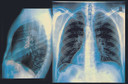

Logo após a colocação dos eletrodos são realizados vários testes para ter-se a certeza de que o aparelho esteja funcionando bem. O paciente deve permanecer em observação no hospital por 12 a 24 horas e antes da alta deverá fazer um eletrocardiograma15 e uma radiografia de tórax16 para verificar se os eletrodos estão na posição correta e para checar seus pulmões17.